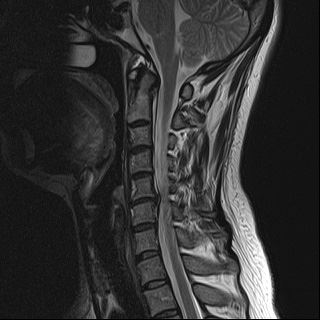

목을 받쳐주는 뼈를 경추라고 하는데 여기는 뼈가 7개 있고 이 뼈 마디마다 디스크라는것이 있습니다. 이 디스크의 역할은 척추 뼈 사이에 충격을 완화하고 운동할 수 있게합니다. 목디스크는 퇴행성 척추 질환으로 목 주위 근육, 인대가 장기간 압력을 받고 퇴행하여, 디스크가 자신의 역할을 하지 못하고 밀려나고 통증과 같은 목디스크 증상을 보이는 질병입니다. 이 디스크의 위치가 어디에 있는지에 따라 목 이외에도, 손이 저리거나 어깨가 아프고 두통과 같은 다른 목 디스크 증상을 일으킬 수 있습니다. 만약 여러분이 디스크를 그대로 방치하면, 몸이 마비되거나 호흡이 곤란한 상황에 처할 수 있기 때문에 여러분의 관심을 필요로 할 것입니다.

척수라는 중추신경이 목뼈를 통과하고 목 아래 감각과 운동신경에 영향을 미치기 때문에 목디스크 증상이 나타날 경우 신속한 대책이 필요합니다. 목디스크 치료는 일반적으로 초기 단계에서 대부분의 환자가 물리 치료 또는 약물을 통해 개선됩니다. 그렇지 않으면 신경 성형술과 차단술이라는 뼈 주사 목 디스크 치료법을 사용합니다.이 치료법은 통증이 나타나는 신경 부위에 약물을 주입하는 것입니다. 치료로 질병을 완전히 치료하는 것이 아니라 염증을 완화하고 통증을 줄이는 것이 중요합니다.

3개월 이상 비수술적 치료를 받았음에도 불구하고, 만약 그들이 호전되지 않는다면, 목디스크 치료 중 수술을 고려할 필요가 있습니다. 인조 디스크를 삽입하기 위해 절개를 통해 디스크를 제거하고 뼈를 하나로 묶는 것과 내시경 수술로 빠져나온 수핵 자체만 제거하는 방법이 있다고 합니다.